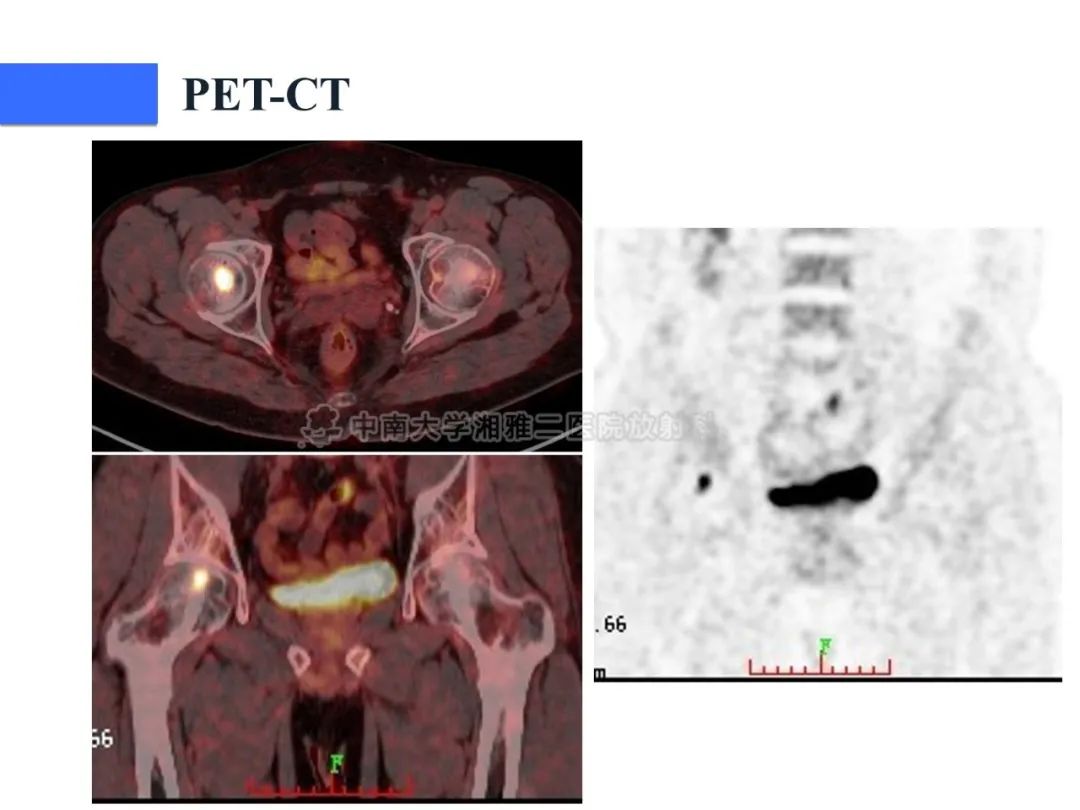

【病例】磷酸盐尿性间叶性肿瘤1例影像学诊断思路-2